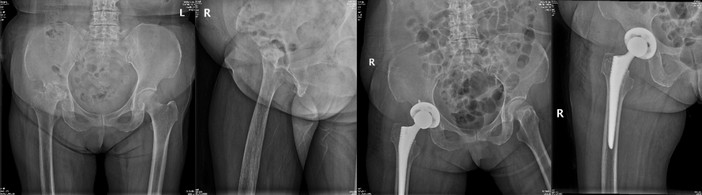

手术治疗

许×,女,66岁,严重股骨头坏死并髋骨关节炎行人工全髋关节置换术,术后3天下地,1周上下楼梯。